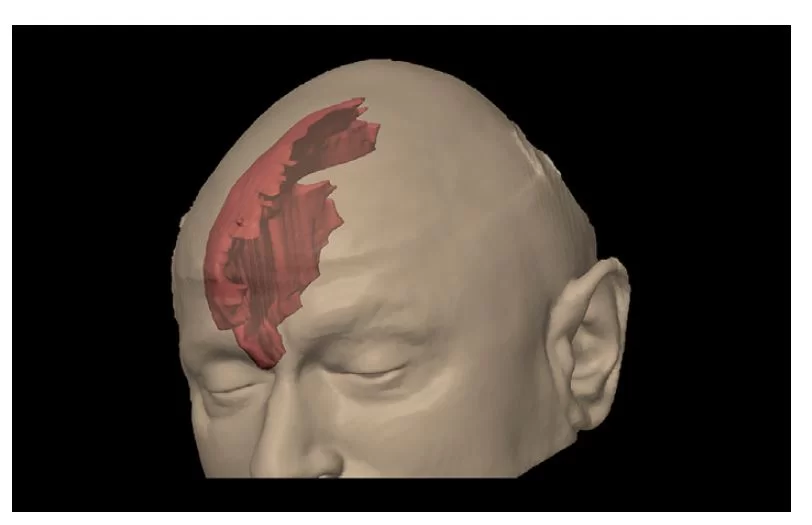

Οι ασθενείς με σημαντική εγκεφαλική ατροφία (Εικόνα 3) διατρέχουν υψηλότερο κίνδυνο για υποσκληρίδιο αιμάτωμα. Αυτή η κατηγορία περιλαμβάνει τους ηλικιωμένους, εκείνους με ιστορικό κατάχρησης αλκοόλ και αυτούς με προηγούμενη τραυματική εγκεφαλική βλάβη. Σε αυτούς τους ασθενείς ακόμα και ασήμαντο τραύμα στο κεφάλι μπορεί να προκαλέσει υποσκληρίδιο αιμάτωμα. Έτσι, το υποσκληρίδιο αιμάτωμα παρατηρείται συχνότερα σε ηλικιωμένους ασθενείς παρά σε νεότερους.